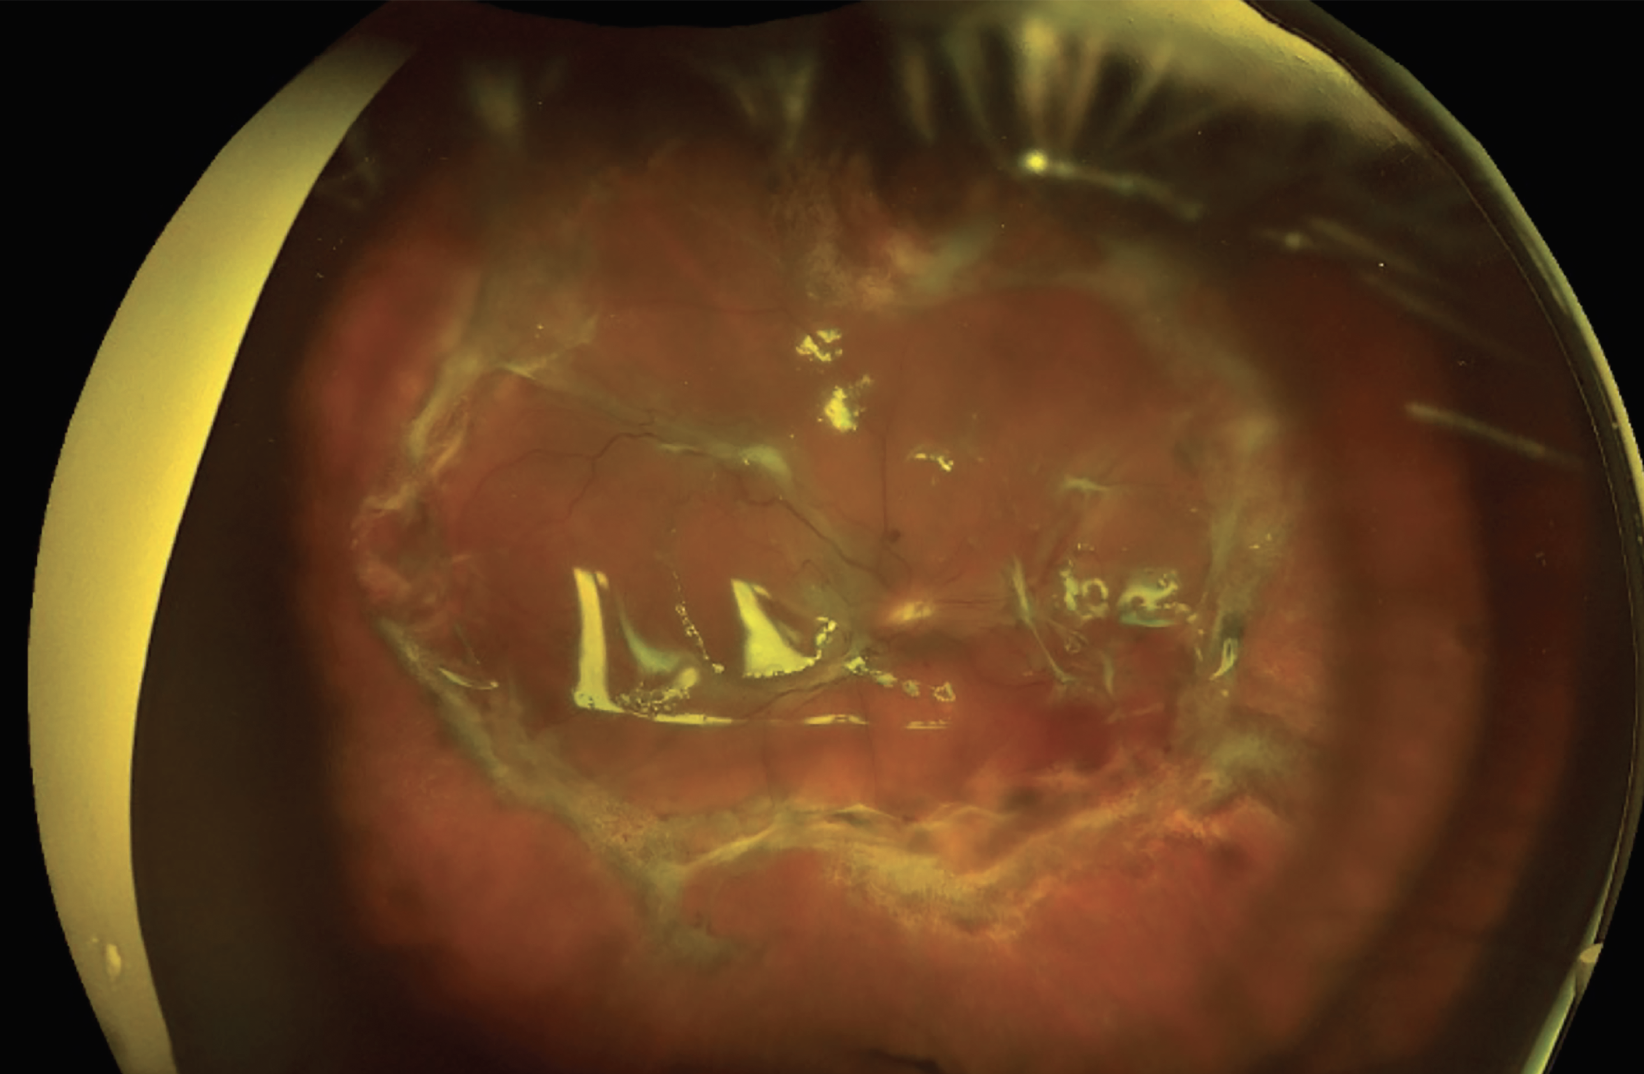

Patients with recurrent detachments secondary to proliferative vitreoretinopathy (Figure 1) who have already had a vitrectomy with silicone oil tamponade can benefit from vitrectomy under silicone oil.

| Figure 1. A recurrent retinal detachment secondary to proliferative vitreoretinopathy before surgery. |